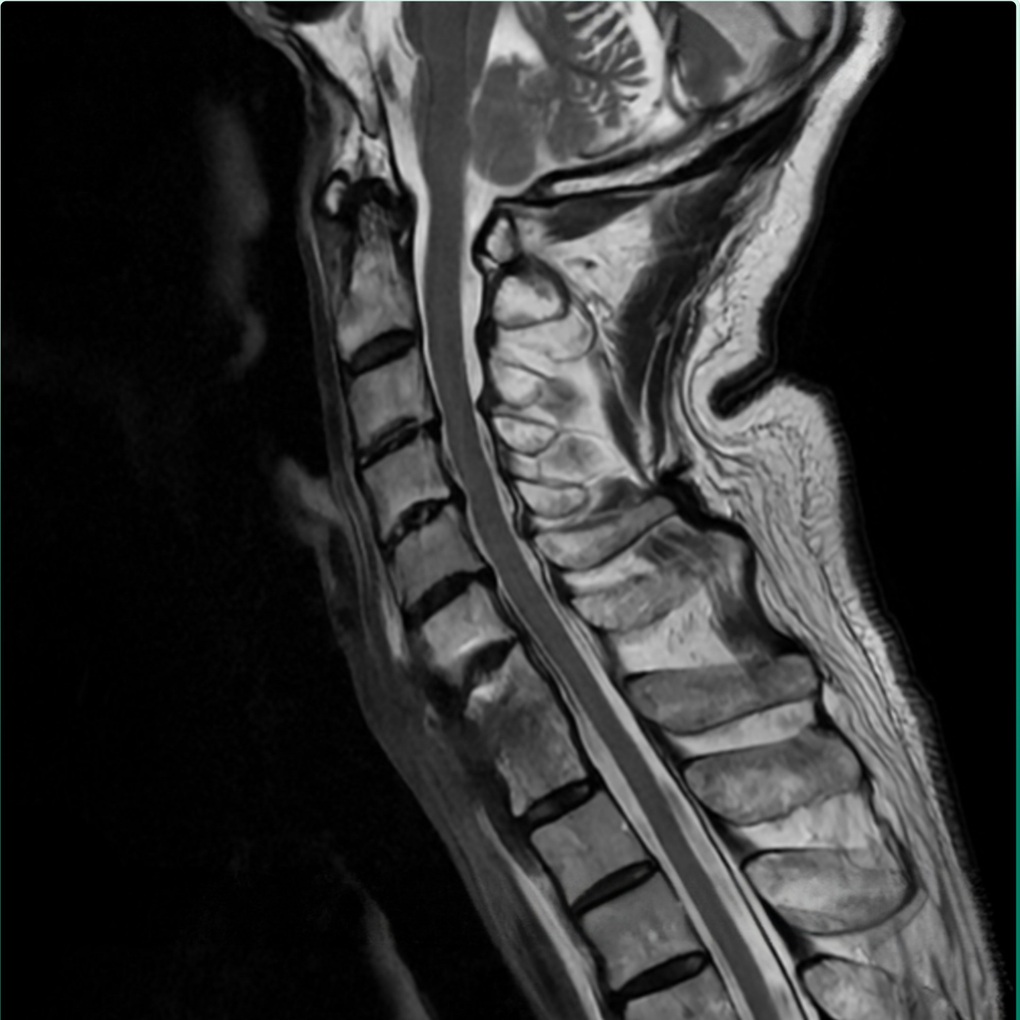

Dải xơ và ổ viêm được xử lý, lấy lại đường cong sinh lý, làm vững cột sống cổ (Ảnh: BVCC).

Dưới sự hỗ trợ của máy C-arm 3D tích hợp trí tuệ nhân tạo AI, sau hơn 2 giờ phẫu thuật PGS. Hà Kim Trung; ThS.BSNT Nguyễn Quang Trung cùng toàn bộ ê-kíp đã thành công bóc tách phần xơ dính, xử lý ổ viêm, làm vững cột sống cổ. Hậu phẫu bệnh nhân tỉnh, tình trạng tê bì, đau mỏi đã cải thiện, không yếu liệt chi, cổ có thể xoay, ngửa nhẹ nhàng.